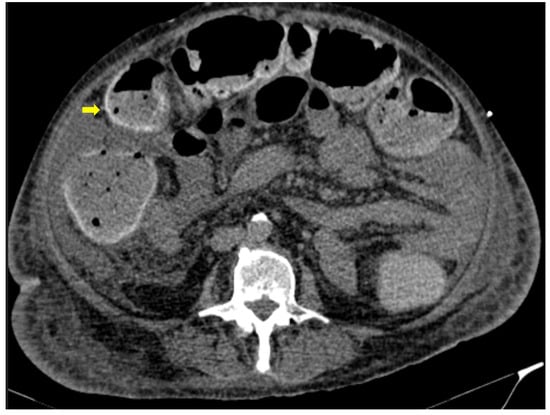

Figure 10. 56-year-old hospitalized male patient with COVID-19 pneumonia with raised level of d-dimers. CT depicting the thrombosed portal vein (yellow arrow). Note that in the same scan, there is extended small bowel thickening with mesenteric free fluid.